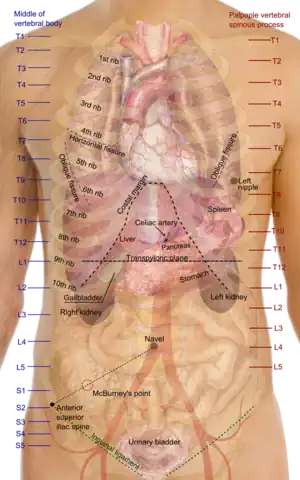

The human abdomen and organs which can be found beneath the surface | |

The abdomen (colloquially called the belly, tummy, midriff, tucky or stomach) is the part of the body between the thorax (chest) and pelvis, in humans and in other vertebrates. The abdomen is the front part of the abdominal segment of the torso. The area occupied by the abdomen is called the abdominal cavity. In arthropods, it is the posterior tagma of the body; it follows the thorax or cephalothorax.[1]

In humans, the abdomen stretches from the thorax at the thoracic diaphragm to the pelvis at the pelvic brim. The pelvic brim stretches from the lumbosacral joint (the intervertebral disc between L5 and S1) to the pubic symphysis and is the edge of the pelvic inlet. The space above this inlet and under the thoracic diaphragm is termed the abdominal cavity. The boundary of the abdominal cavity is the abdominal wall in the front and the peritoneal surface at the rear.

In vertebrates, the abdomen is a large body cavity enclosed by the abdominal muscles, at the front and to the sides, and by part of the vertebral column at the back. Lower ribs can also enclose ventral and lateral walls. The abdominal cavity is continuous with, and above, the pelvic cavity. It is attached to the thoracic cavity by the diaphragm. Structures such as the aorta, inferior vena cava and esophagus pass through the diaphragm. Both the abdominal and pelvic cavities are lined by a serous membrane known as the parietal peritoneum. This membrane is continuous with the visceral peritoneum lining the organs.[2] The abdomen in vertebrates contains a number of organs belonging to, for instance, the digestive system, urinary system, and muscular system.

The abdominal cavity contains most organs of the digestive system, including the stomach, the small intestine, and the colon with its attached appendix. Other digestive organs are known as the accessory digestive organs and include the liver, its attached gallbladder, and the pancreas, and these communicate with the rest of the system via various ducts. The spleen, and organs of the urinary system including the kidneys, and adrenal glands also lie within the abdomen, along with many blood vessels including the aorta and inferior vena cava. The urinary bladder, uterus, fallopian tubes, and ovaries may be seen as either abdominal organs or as pelvic organs. Finally, the abdomen contains an extensive membrane called the peritoneum. A fold of peritoneum may completely cover certain organs, whereas it may cover only one side of organs that usually lie closer to the abdominal wall. This is called the retroperitoneum, and the kidneys and ureters are known as retroperitoneal organs.

Different medical procedures can be used to examine the organs of the gastrointestinal tract. These include endoscopy, colonoscopy, sigmoidoscopy, enteroscopy, oesophagogastroduodenoscopy and virtual colonoscopy. There are also a number of medical imaging techniques that can be used. Surface landmarks are important in the examination of the abdomen.

Surface landmarks

In the mid-line, a slight furrow extends from the xiphoid process above to the pubic symphysis below, representing the linea alba in the abdominal wall. At about its midpoint sits the umbilicus or navel. The rectus abdominis on each side of the linea alba stands out in muscular people. The outline of these muscles is interrupted by three or more transverse depressions indicating the tendinous intersections. There is usually one about the xiphoid process, one at the navel, and one in between. It is the combination of the linea alba and the tendinous intersections which form the abdominal "six-pack" sought after by many people.

The upper lateral limit of the abdomen is the subcostal margin (at or near the subcostal plane) formed by the cartilages of the false ribs (8, 9, 10) joining one another. The lower lateral limit is the anterior crest of the ilium and Poupart's ligament, which runs from the anterior superior spine of the ilium to the spine of the pubis. These lower limits are marked by visible grooves. Just above the pubic spines on either side are the external abdominal rings, which are openings in the muscular wall of the abdomen through which the spermatic cord emerges in the male, and through which an inguinal hernia may rupture.

One method by which the location of the abdominal contents can be appreciated is to draw three horizontal and two vertical lines.

Horizontal lines

- The highest of the former is the transpyloric line of C. Addison, which is situated halfway between the suprasternal notch and the top of the pubic symphysis, and often cuts the pyloric opening of the stomach an inch to the right of the mid-line. The hilum of each kidney is a little below it, while its left end approximately touches the lower limit of the spleen. It corresponds to the first lumbar vertebra behind.

- The second line is the subcostal line, drawn from the lowest point of the subcostal arch (tenth rib). It corresponds to the upper part of the third lumbar vertebra, and it is an inch or so above the umbilicus. It indicates roughly the transverse colon, the lower ends of the kidneys, and the upper limit of the transverse (3rd) part of the duodenum.

- The third line is called the intertubercular line, and runs across between the two rough tubercles, which can be felt on the outer lip of the crest of the ilium about two and a half inches (64 mm) from the anterior superior spine. This line corresponds to the body of the fifth lumbar vertebra, and passes through or just above the ileo-caecal valve, where the small intestine joins the large intestine.

Vertical lines

The two vertical or mid-Poupart lines are drawn from the point midway between the anterior superior spine and the pubic symphysis on each side, vertically upward to the costal margin.

- The right one is the most valuable, as the ileo-caecal valve is situated where it cuts the intertubercular line. The orifice of the appendix lies an inch lower, at McBurney's point. In its upper part, the vertical line meets the transpyloric line at the lower margin of the ribs, usually the ninth, and here the gallbladder is situated.

- The left mid-Poupart line corresponds in its upper three-quarters to the inner edge of the descending colon.

The right subcostal margin corresponds to the lower limit of the liver, while the right nipple is about half an inch above its upper limit.

Quadrants and regions

The abdomen can be divided into quadrants or regions to describe the location of an organ or structure. Classically, quadrants are described as the left upper, left lower, right upper, and right lower. Quadrants are also often used in describing the site of an abdominal pain.[15]

The abdomen can also be divided into nine regions.